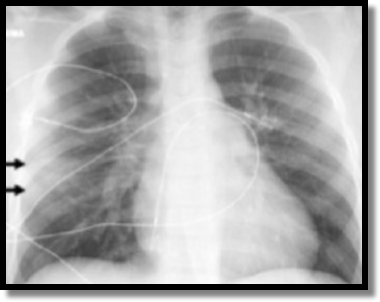

Pediatric Pulmonary Contusion

- CT does define pulmonary contusion earlier than CXR.

- CT does define lung volume involved better than CXR.

- But CXR findings correlate with length of hospital stay, # of ICU days, and # of ventilator days.

- Pulmonary contusion not seen on CXR but picked up on CT is not as significant as pulmonary contusion seen on CXR. If the less sensitive study finds the condition, the condition is likely worse (my simple minded way of thinking of it).